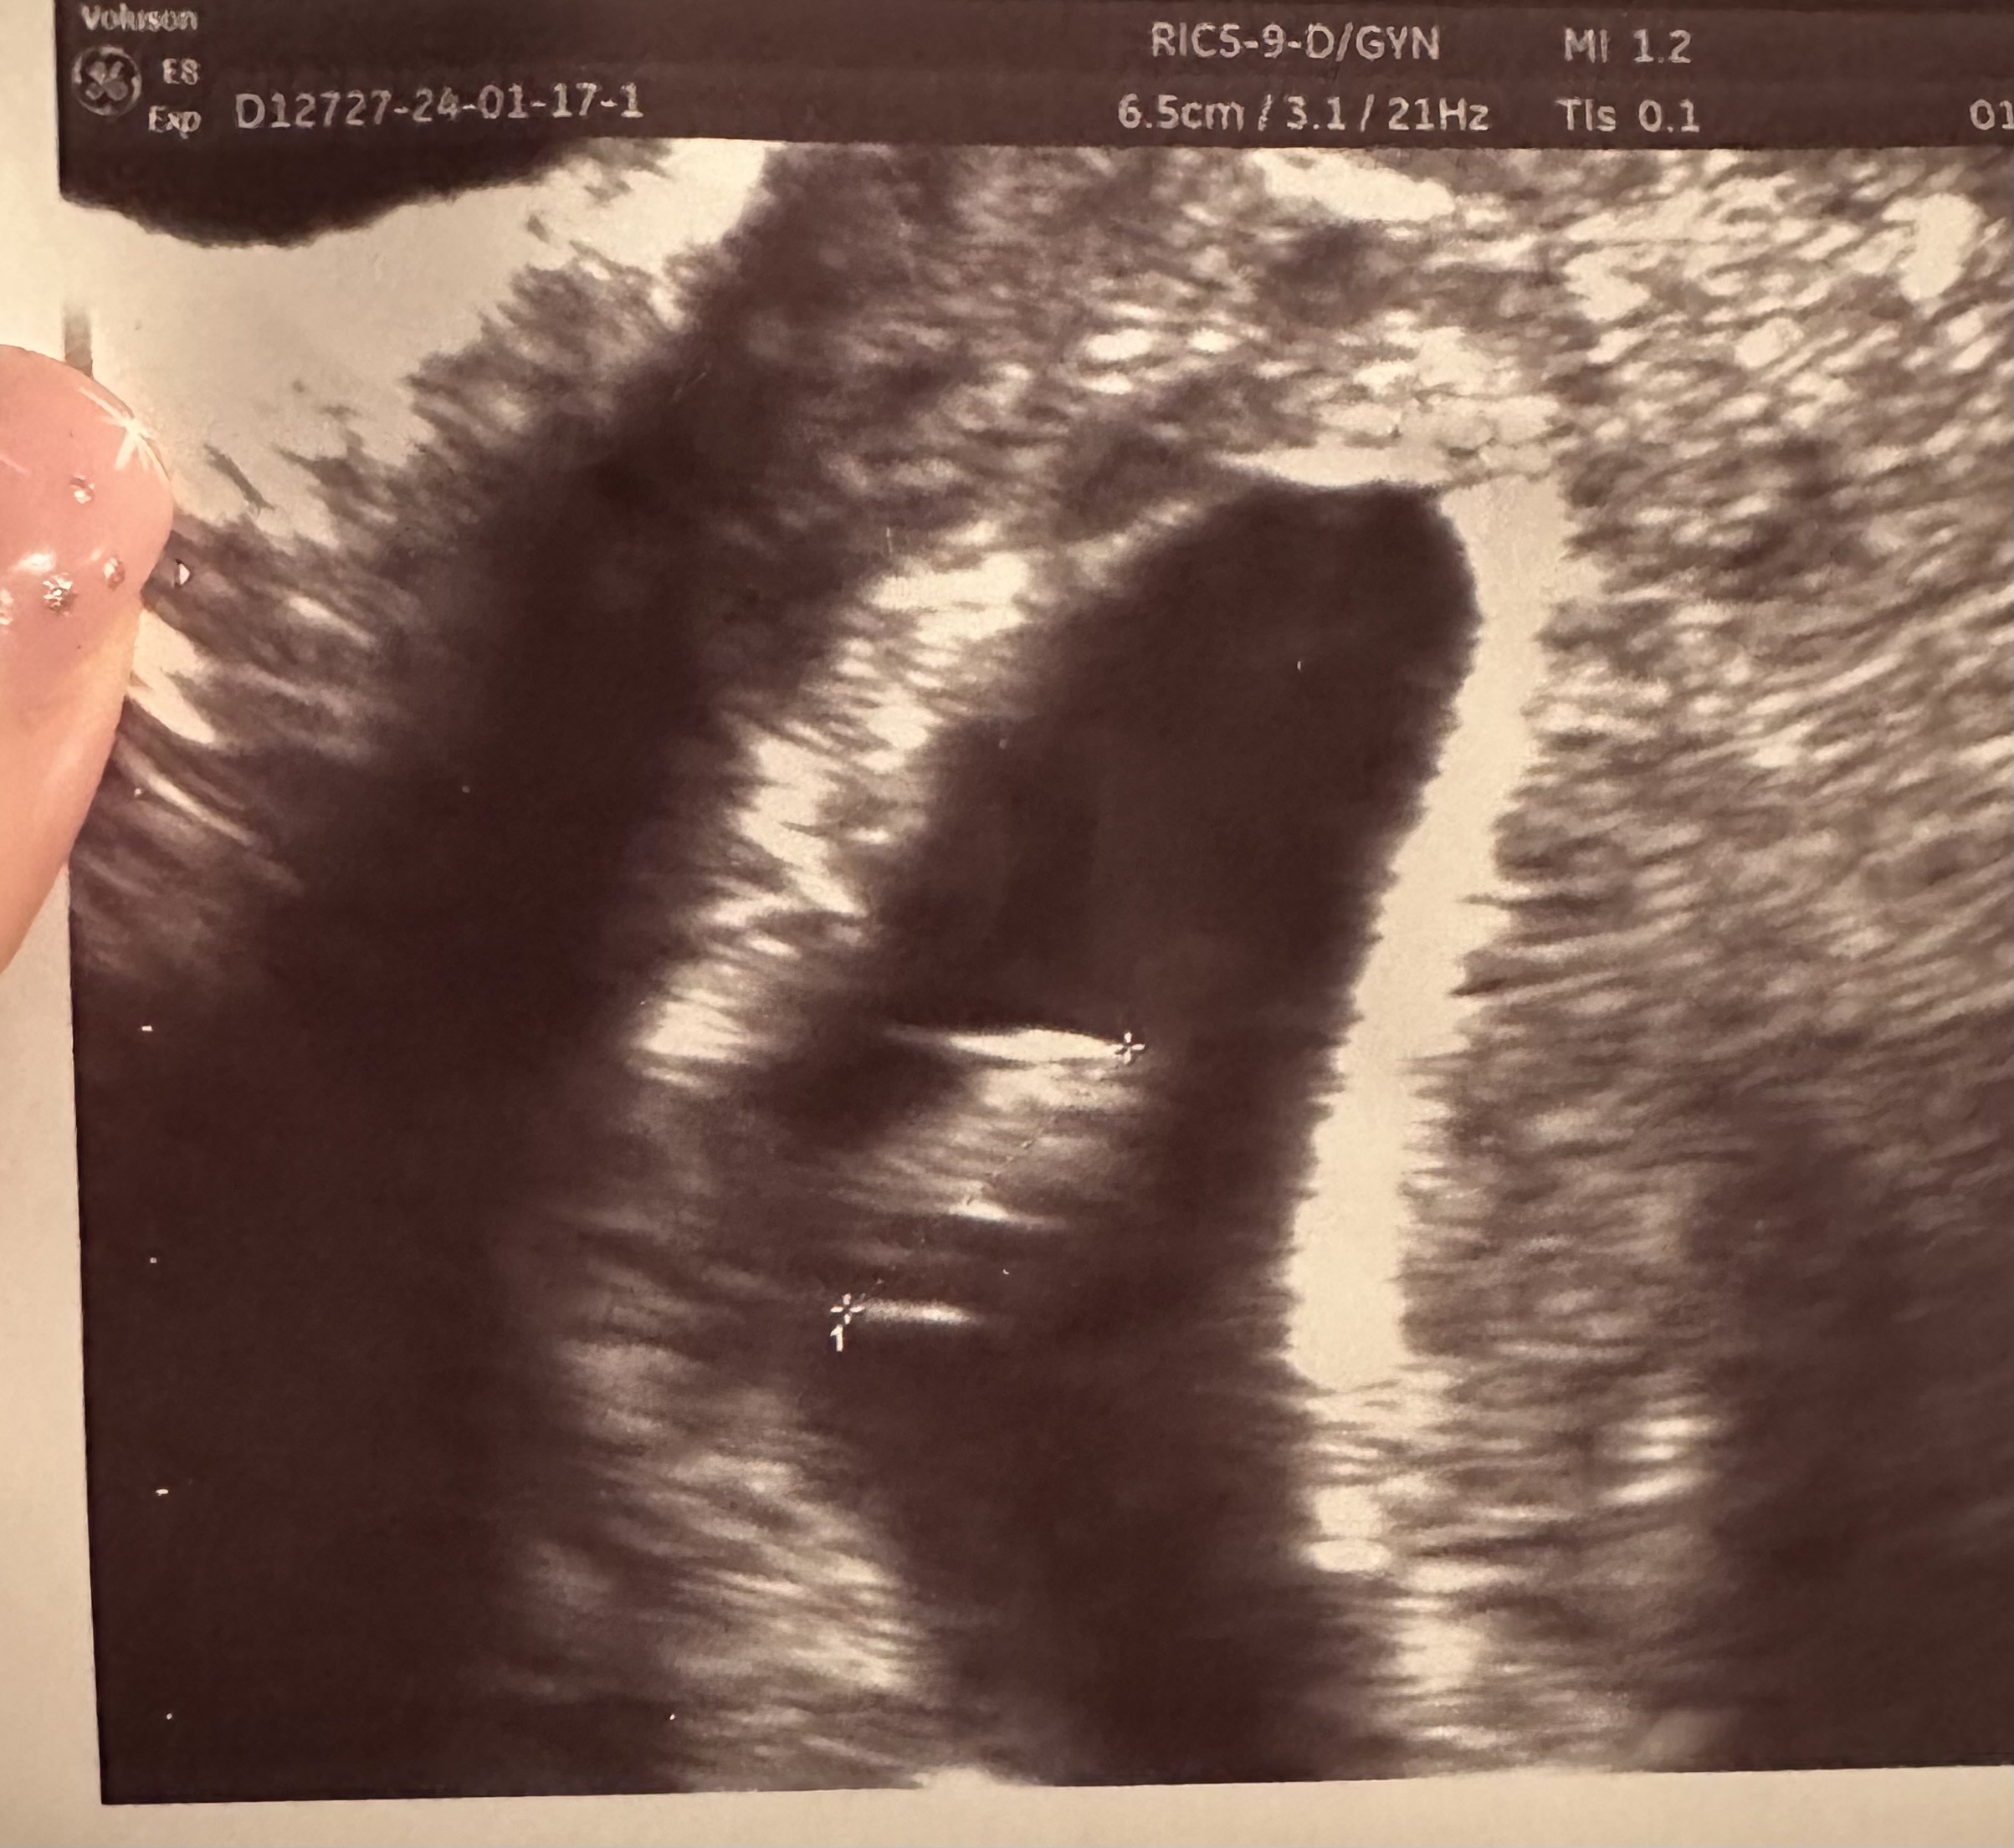

Zdjęcie z ostatniej wizyty :)

Załączniki

• 18085403-a557-43c4-bf0f-7caf87dfc387.jpeg

18085403-a557-43c4-bf0f-7caf87dfc387.jpeg

25,4 KB · Wyświetleń: 150